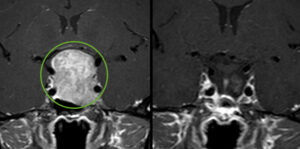

Over a few weeks in the summer of 2014, Donatella developed intense right face pain; it hurt so much she couldn’t eat, and could hardly speak. A brain MRI showed a tumor affecting the right trigeminal nerve in the base of the skull. Most doctors initially thought this was a benign tumor of the cranial nerves called a trigeminal schwannoma. As we are Italians, we travelled all around Italy asking many neurosurgeons what they thought about it and how they would have operated. There were a lot of risks, none of them felt sure of operating because the probability of damaging her optic and auditory nerves was high as well as the risk of compromising her breathing and balance. Most of them wanted to operate through a craniotomy with a 9-day recovery but none were sure that the surgical operation would work.

We were really afraid of the uncertainty of Italian doctors and so we kept looking for a different solution when I did a web search for this pathology in English and I found Dr. Daniel Kelly. We emailed Dr. Kelly at the address we found on the website. Dr. Kelly was immediately helpful: he replied that we could send him through the cloud the MRI and he would give his medical report. In a few days Dr. Kelly called us on Skype and told us that my mother could have a schwannoma but probably she had something worse, possibly a malignant tumor. He didn’t think a craniotomy was the right option and he suggested to do a minimal invasive surgery called neuro-endoscopy (an operation through the nose to reach the tumor in the skull base with a two day recovery). We still had a lot of doubts, but Dr. Kelly’s availability, kindness, professionalism and great humanity made us believe in this chance, and finally we left for Los Angeles.

When Dr. Kelly and Dr. Griffiths operated they discovered, as suspected from studying the MRI, that the tumor was not benign but it was something different – a lymphoma affecting the trigeminal nerve, a rare and aggressive disease. Dr. Kelly said they knew how to treat this problem, analyze the tissue and arranged an appointment with a Saint John’s oncologist Dr. Sean Fischer. During the operation the bone around the nerve and tumor was removed and the trigeminal nerve was biopsied to obtain a diagnosis and to provide nerve decompression . Within a day of the surgery and nerve decompression my mother gradually began to feel better, allowing her to speak and eat without pain. Before the surgery, she had lost 20 kg (44 lbs) in a month because she couldn’t eat.